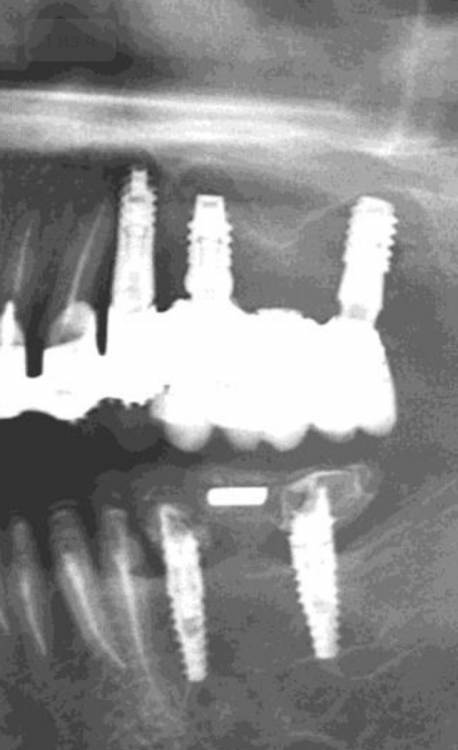

annda Опубликовано 29 апреля, 2021 Поделиться Опубликовано 29 апреля, 2021 (изменено) Интересующая область-14. Пациентка обратилась для протезирования дефектов полости рта.Было предложено удалить весь верх и низ.На верху было предложено все на 6,внизу все на 4х,но решила сделать все на 5(а вот так вот). Поступил категорический отказ удалять верхние передние зубы(на приеме подвижность 1-2й степени).Тогда как альтернатива предложен съемник на локаторах как временный вариант(с тайной мыслью-"вот поносишь и все равно придешь за первым вариантом") На операции одномоментное удаление боковых верхних и низа,установка имплантатов,формики и нагрузка в соответствии с торками.Дикий дефект в области 14 просто откюретажили до костной ткани,грануляции вырезали. Через 4 месяца приносит новую КТ.Я просто онемела.Зубы на верхней челюсти неподвижны от слова совсем...Вот что это было и есть?? Изменено 29 апреля, 2021 пользователем annda 1 Ссылка на комментарий

annda Опубликовано 29 апреля, 2021 Автор Поделиться Опубликовано 29 апреля, 2021 По протезке не было ничего, от слова совсем. Даже кривые настройки КТ не могут так исказить картину:))Срезы одни и те же , видны на обоих снимках, зубы центральные принадлежат одному человеку. Кстати, 68 лет от роду... Кость уже пощупала фрезой, абсолютно полноценная костяка... Ссылка на комментарий